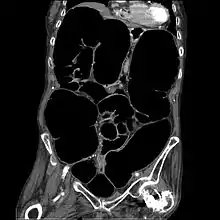

متلازمة أوغيلفي هي اتساع حاد في القولون في حالة عدم وجود أي عوائق ميكانيكية في المرضى الذين يعانون من آلام مبرحة.[1]

يتميز القولون الزائف بوجود العراقيل التي تؤدي إلى توسع هائل في الأعور (قطر أكبر من 10 سم) والقولون الأيمن على البطن للأشعة السينية.[2][3] هو نوع من تضخم القولون، الذي يشار إليه أحيانا باسم "تضخم القولون الحاد"، لتمييزه عن تضخم القولون السام.